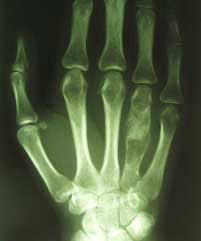

Großer Knochentumor

(Enchondrom)

im

4. Mittelhandknochen